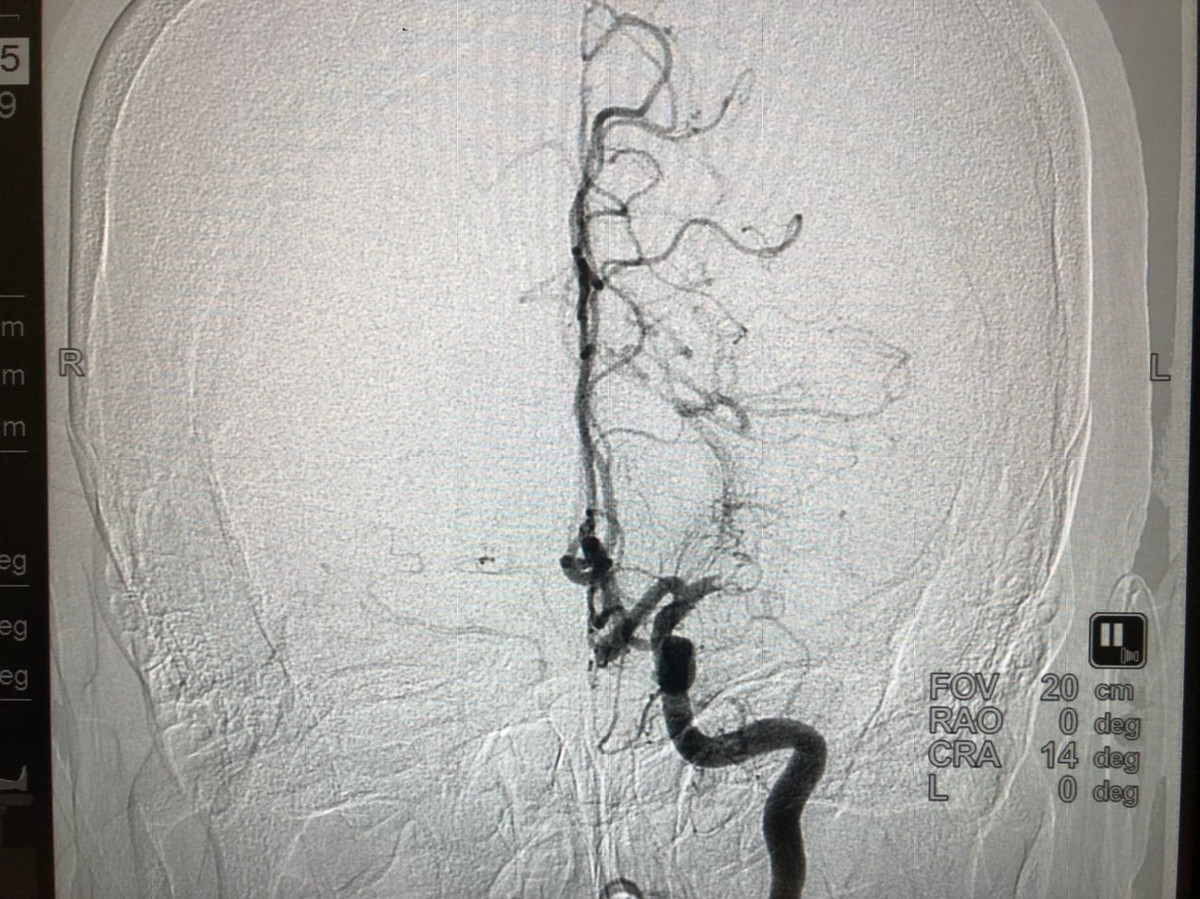

![]() |

| Hình ảnh tắc mạch máu não được chụp trên hệ thống chấn đoán hình ảnh DSA cao cấp của BV Vinmec Đà Nẵng. |